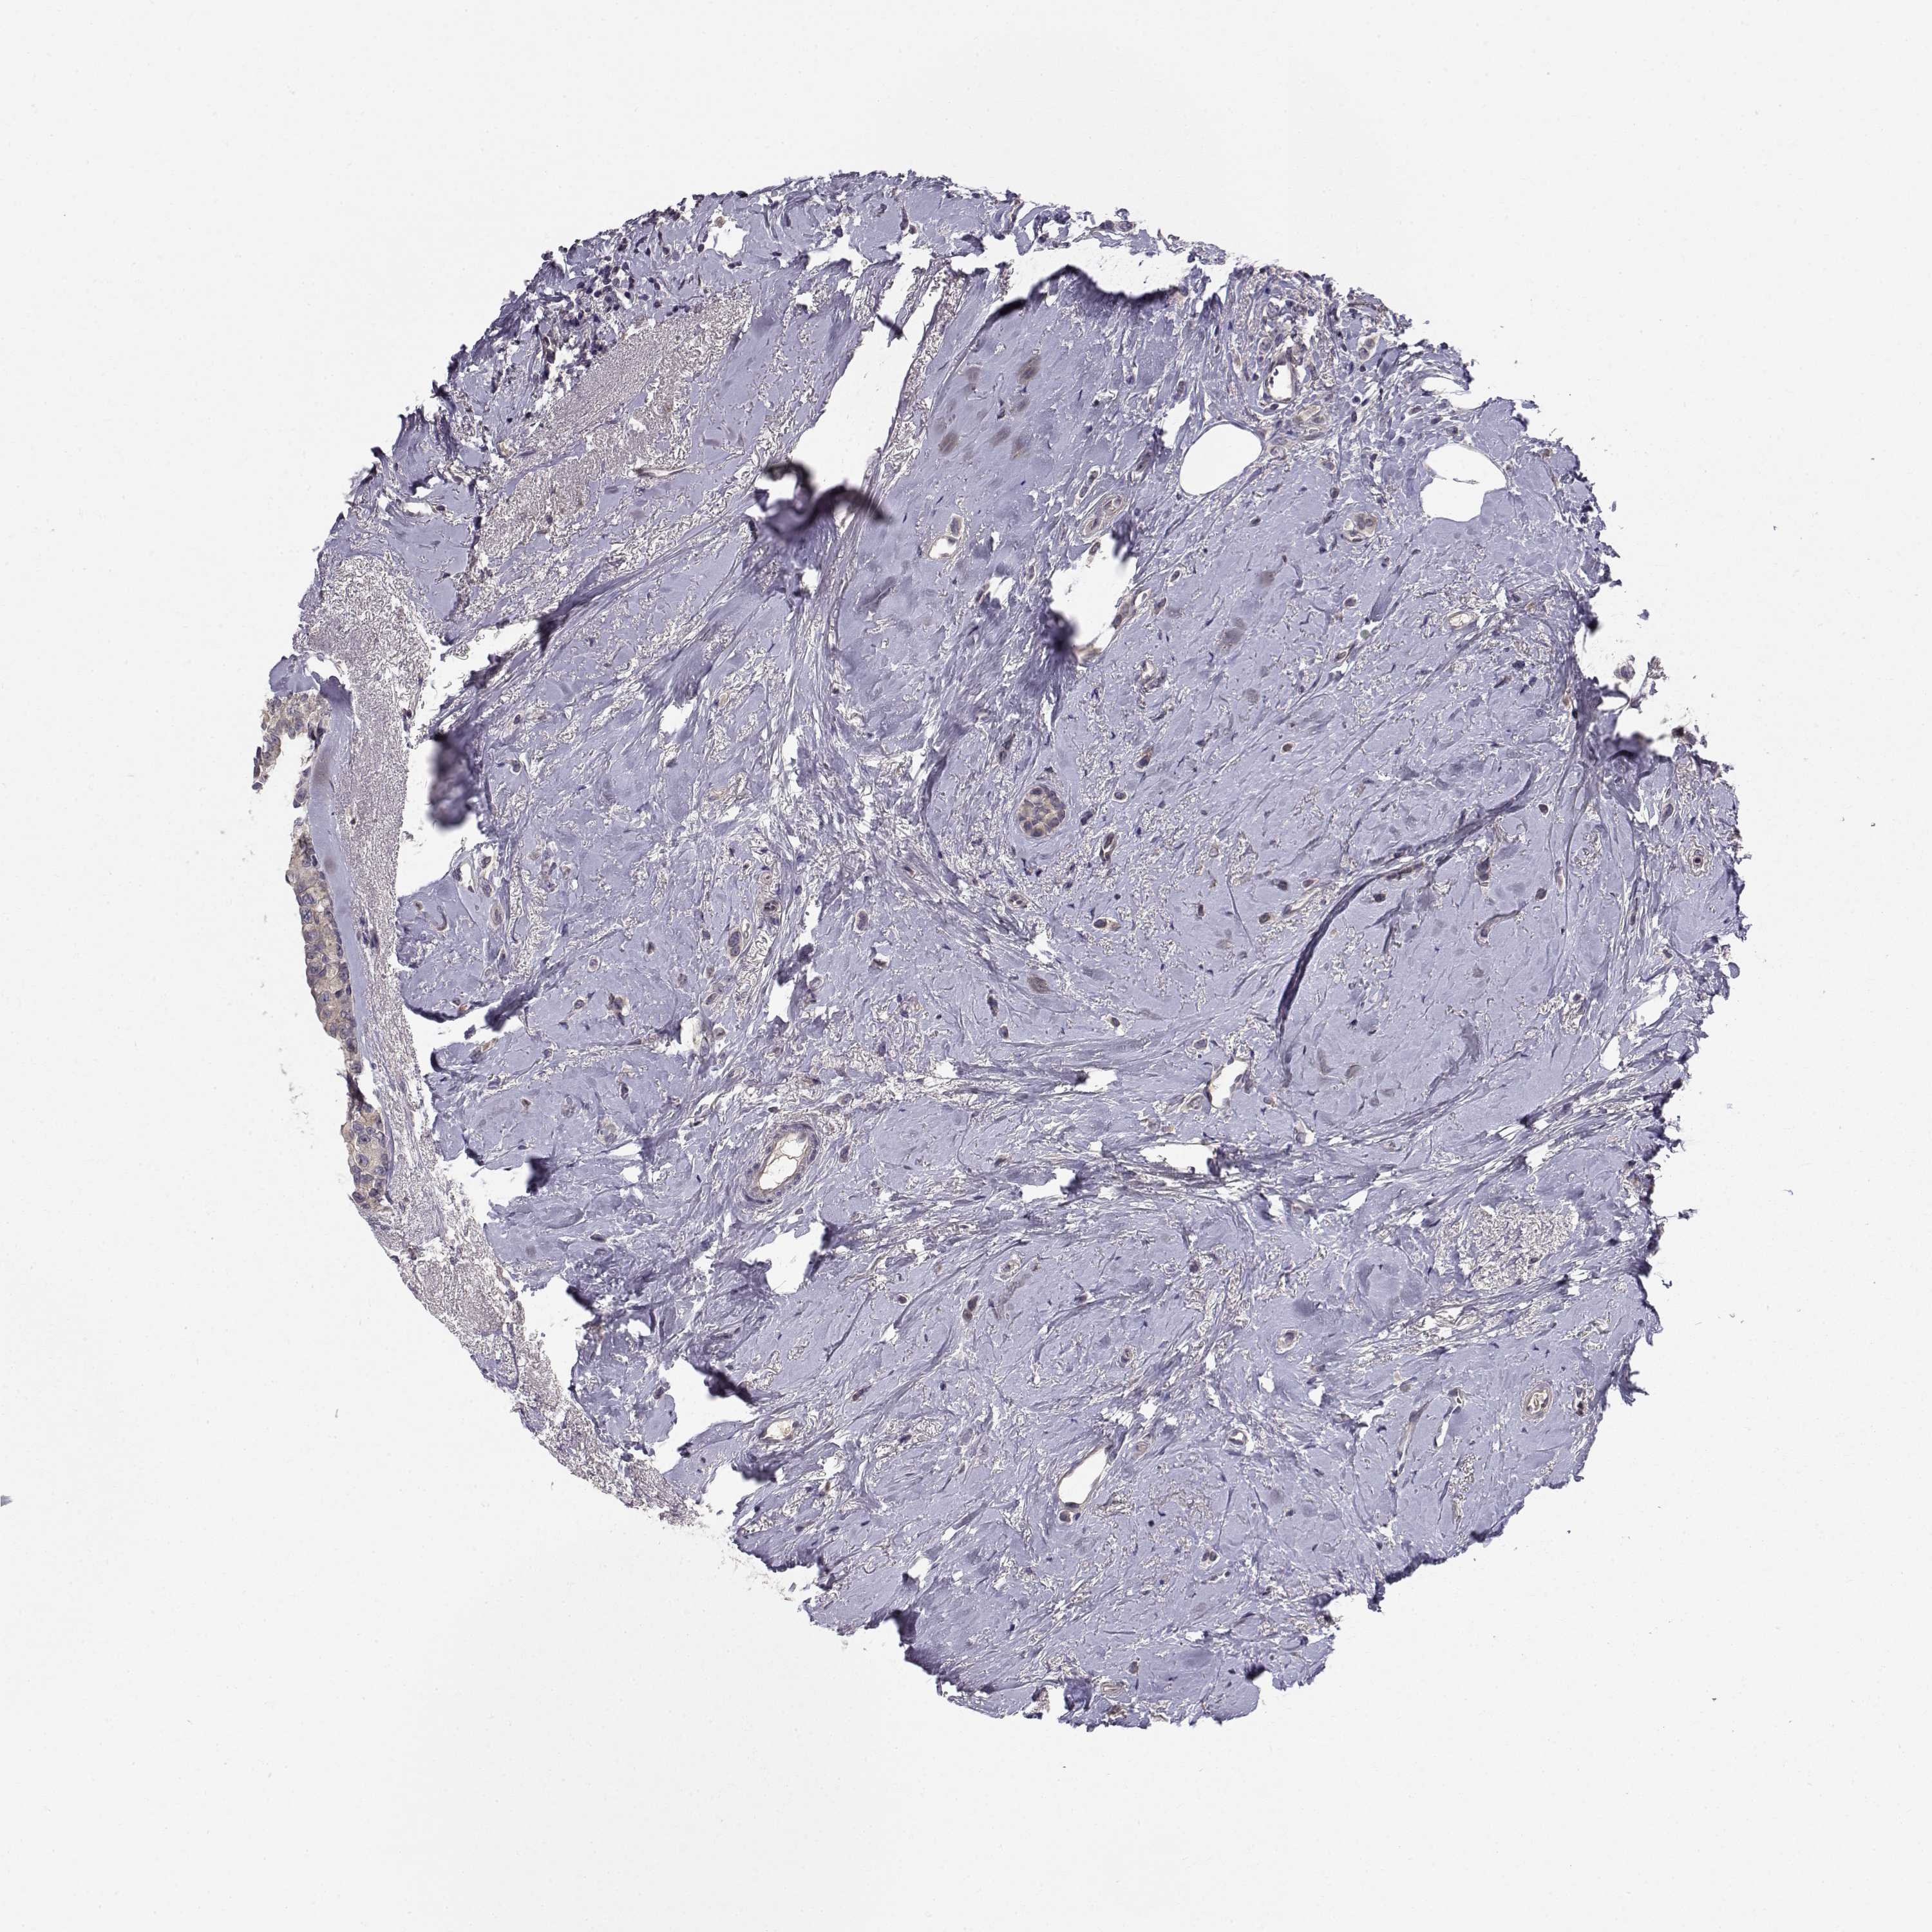

CANCER BREAST CANCER Show tissue menu

BRCA TCGA BRCA VALIDATION PROTEIN EXPRESSION